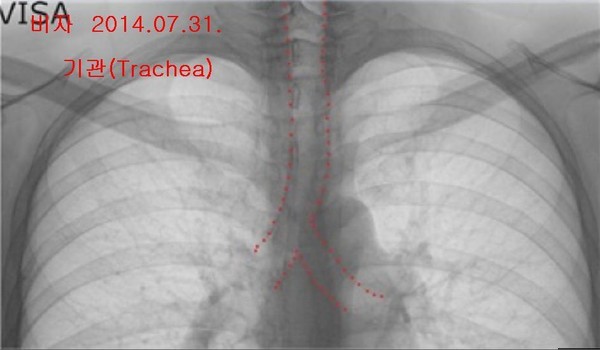

- ▲ 양승오 박사 재판 피고인들이, 유력한 증거로 꼽고 있는 박주신씨 명의의 엑스레이 3장. 왼쪽부터 공군훈련소(2011년 8월 촬영)-자생병원(2011년 12월 촬영)-비자발급용 엑스레이(2014년 7월 촬영). ⓒ 뉴데일리DB

박주신씨의 신체를 촬영한 것으로 알려진 엑스레이는 모두 3장이 있다. 이 중, ‘공군훈련소 입소 당시 엑스레이’(촬영일자 2011년 8월 30일, 이하 공군 엑스레이)와, 주신씨가 ‘비자발급을 위해 촬영한 세브란스병원 엑스레이’(촬영일자 2014년 7월 31일, 이하 비자발급용 엑스레이)는 피고인들도 박주신씨 본인의 것으로 보고 있다.

반면 피고인들은, 박주신씨가 병역처분 변경을 위해 병무청에 제출한 자생병원 엑스레이(촬영일자 2011년 12월 9일)는, 주신씨가 아닌 대리신검자의 것으로 의심하고 있다.

양승오 박사는 “공군에서 찍은 엑스레이와 비자발급을 위해 찍은 엑스레이에서는 피사체의 제1흉추와 제7경추 극상돌기가 오른쪽으로 휘어있지만, 자생병원에서 찍은 영상에서는 정방향으로 나온다”며, “이 2개만 가지고도 동일인으로 볼 수 없다”는 소견을 밝혔다.

이어 양 박사는 박주신씨 명의 엑스레이 3장에서 공군-비자발급용 엑스레이와 달리 자생병원 엑스레이에서만, 기관(氣管)의 모양이 다른 점, 흉곽의 좌우 길이가 더 긴 점 등을 근거로 들며, 피사체를 동일인으로 볼 수 없다는 의견을 나타냈다.

- ▲ 박주신씨 명의 엑스레이 3장에서 나타나는 기관(氣管)의 주행 형태. 자생병원 엑스레이는 직선으로 뻗어 있으나, 공군-비자발급용 엑스레이는 왼쪽으로 휘어있다. ⓒ 의료혁신투쟁위 제공